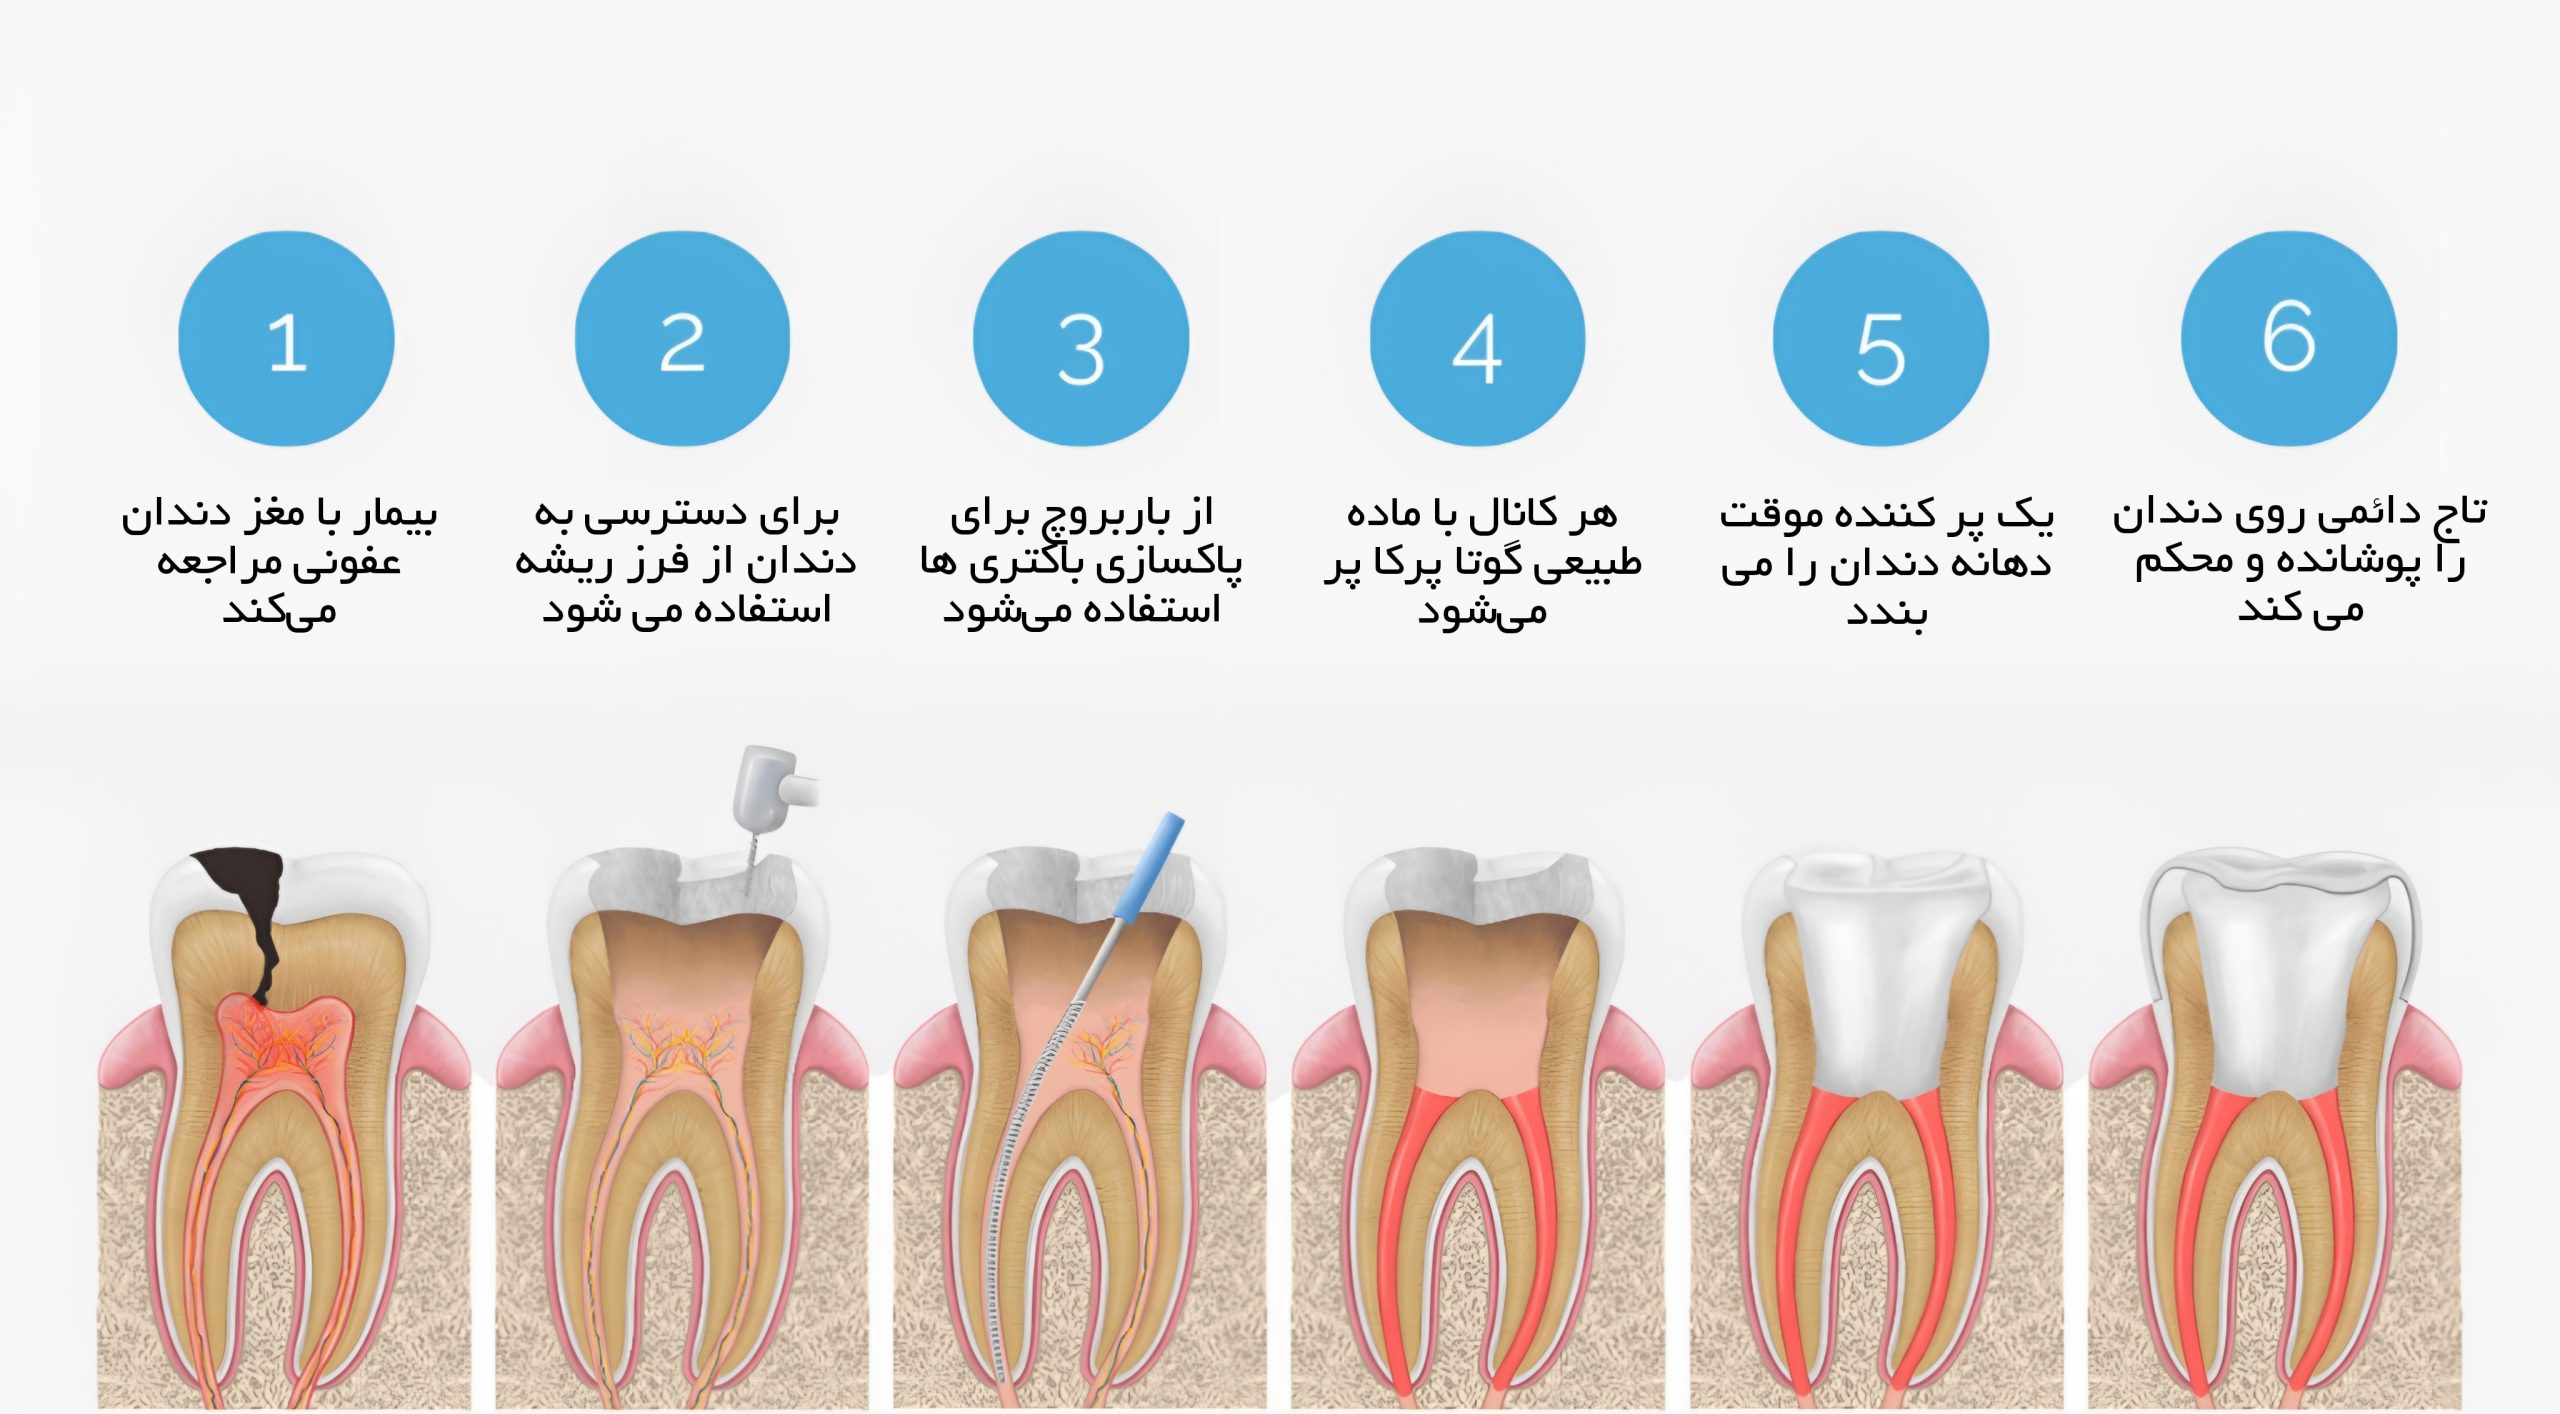

مراحل درمان ریشه دندان یا عصب کشی دندان

در مرحله اول ابتدا، برای انجام معاینه و بررسی وضعیت و میزان آسیب دندان عکس رادیولوژی (عکس opg )از دندان گرفته می شود. به منظور این که درد هنگام انجام درمان ریشه دندان فرد را اذیت نکند، از داروی بی حسی موضعی برای جلوگیری از احساس درد استفاده می شود. البته درد هنگام عصب کشی دندان ممکن است به خاطر آبسه و عفونت دندان بسیار زیاد باشد. بعد از بی حس کردن دندان، میله پلاستیکی برای خارج کردن بزاق دهان، داخل دهان بیمار قرار داده می شود.. سپس پوسیدگی هایی که در دندان ایجاد شده است، برداشته شده و عاج دندان برای دسترسی به ساقه پالپ دندان باز می شود. و از یک ابزار کوچک هم برای خارج کردن عفونت ها استفاده می شود.

در مرحله دوم عصب کشی دندان پس از برداشتن پالپ آسیب دیده، ساقه پالپ و کانال های ریشه خالی و تمیز می شوند. این مهم است که قبل از پر کردن دائم کانال های ریشه، تمامی بخش های کانال از تمام عفونت ها پاک شده و خشک شوند. البته این نکته را هم باید بگوییم که هنگام تمیز و خالی کردن کانال های دندان، کانال های ریشه دندان ممکن است تغییر شکل بدهند و بزرگ شوند تا به دسترسی برای پر کردن دندان راحت تر انجام شود. بعد از خالی کردن و تمیز کردن کانال دندان داروهایی به منظور تمیز کردن و خالی کردن دندان ار هرگونه عفونتی داخل کانال دندان ریخته می شود و ممکن است دندان بیمار برای خارج شدن مایع و ترشحات احتمالی از آن برای چند روز باز باقی بماند. اگر عفونت به لایه های داخلی دندان یعنی ریشه دندان نفوذ کرده باشد، ممکن است برای بیمار آنتی بیوتیک تجویز شود. چنانچه درمان ریشه دندان نیازمند چند جلسه درمان باشد، دندان را به صورت موقت پر می کنند تا دندان از مواد غذایی و تماس با بزاق دور نگه داشته شود. در هر صورت در این مدت از جویدن یا گاز گرفتن با استفاده از دندانی که در حال عصب کشی است تا زمانی که دندان درمان شده و ترمیم شود، پرهیز کنید.

پس از خالی کردن عفونت ها به صورت کامل و خشک کردن دندان، کانال دندان پر می شود. در این مرحله ممکن است نیاز به تزریق مواد بی حسی باشد. اگر همانطور که در مرحله دوم گفته شد دندان شما به صورت موقتی پر شده باشد، ابتدا این پر کردگی برداشته می شود تا به این ترتیب بتوان به ناحیه داخل دندان دسترسی پیدا کرد. در این مرحله از مواد مخصوص دندان پزشکی برای پر کردن دندان استفاده می شود تا به این ترتیب بتوان از حفاظت کانال های ریشه در برابر بزاق و نفوذ مواد خارجی اطمینان پیدا کرد.

همان مرحله ترمیم دندان می باشد. به دلیل اینکه دندان معمولاً در این حالت به دلیل پوسدگی زیاد صعیف شده است و به صورت زیاد پر شده است لازم است به منظور حفاظت از آن در برابر آسیب های آتی و نیز کمک به بازگشت دندان به عملکرد طبیعی آن ترمیم دندان انجام شود. انجام ترمیم دندان به وسیله روکش دندان صورت می گیرد که باعث می شود دندان طبیعی به نظر برسد. روکش دندان معمولا از جنس طلا، پرسلن یا ترکیبی از پرسلن و فلز ساخته می شود. روکش ساخته شده از پرسلن یا ترکیب پرسلن و فلز می تواند سایه زده شود تا به رنگ سفید دربیاید و تفاوتی با سایر دندان ها نداشته باشد.